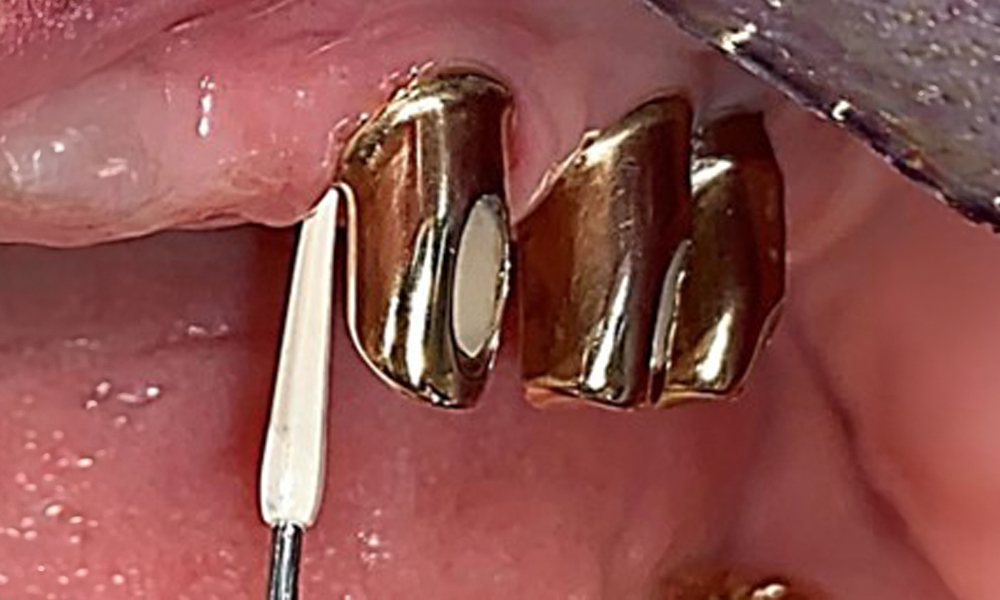

Processing the implant surface with manual titanium instruments.

Fig. 10: Processing the implant surface with manual titanium instruments.

Sonic/ultrasonic, or conventional manual instruments may be used to remove calculus and concretions present on the natural teeth (8). Titanium or plastic curettes (Fig. 10), or a plastic or PEEK attachment (Fig. 11) during ultrasonic treatment, should be used to remove mineralized plaque from implants to avoid damaging the implant surfaces.